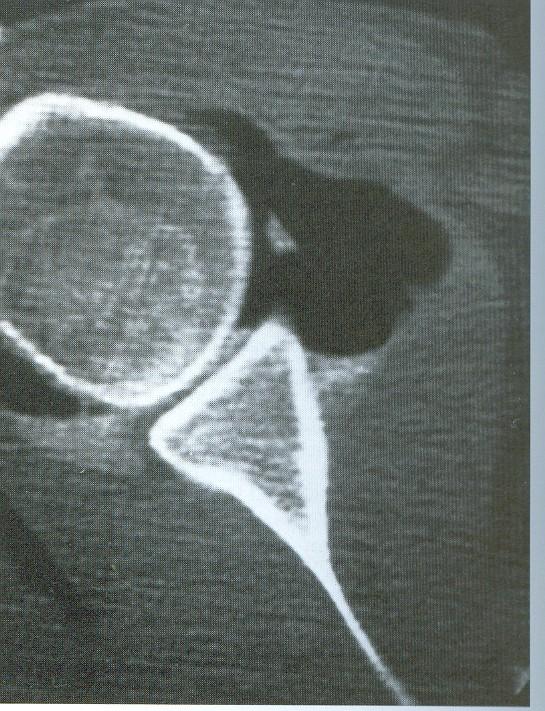

Artrografía…

Indicaciones de la Artrografía • Ruptura del Maguito de los Rotadores • Capsulitis Adhesiva • Alteraciones del Tendón del Bíceps • Luxaciones Crónicas • Evaluación de Inflamación Sinovial • Hombro Congelado

Artrografía